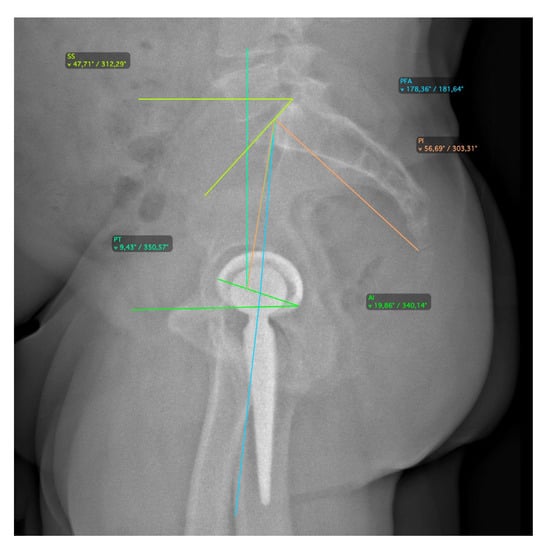

2.2. Radiographic Assessment